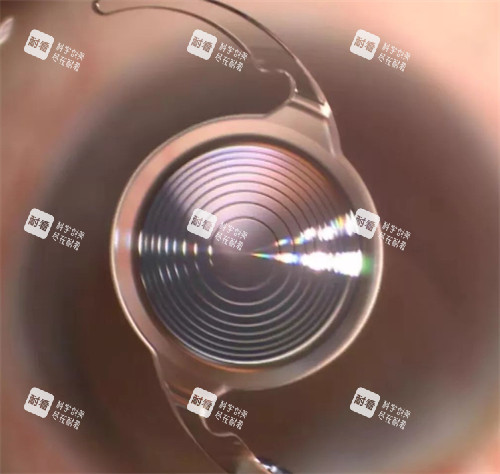

较高的治疗技术:爱尔眼科医院采用了国内外较高的超声乳化技术。

这种技术通过微小切口将混浊的晶状体乳化吸出,再植入人工晶状体,具有切口小、修复快、术后散光小等优点。

多样化的治疗方案:华厦眼科医院除了常见的超声乳化技术外,还提供飞秒激光辅助白内障手术。

飞秒激光能够更更好地制作切口和撕囊,提高手术的靠谱性和较准性。

例如,他们研发的新型人工晶状体,能够更好地模拟人眼的自然调节功能,提高患者的术后视觉质量。